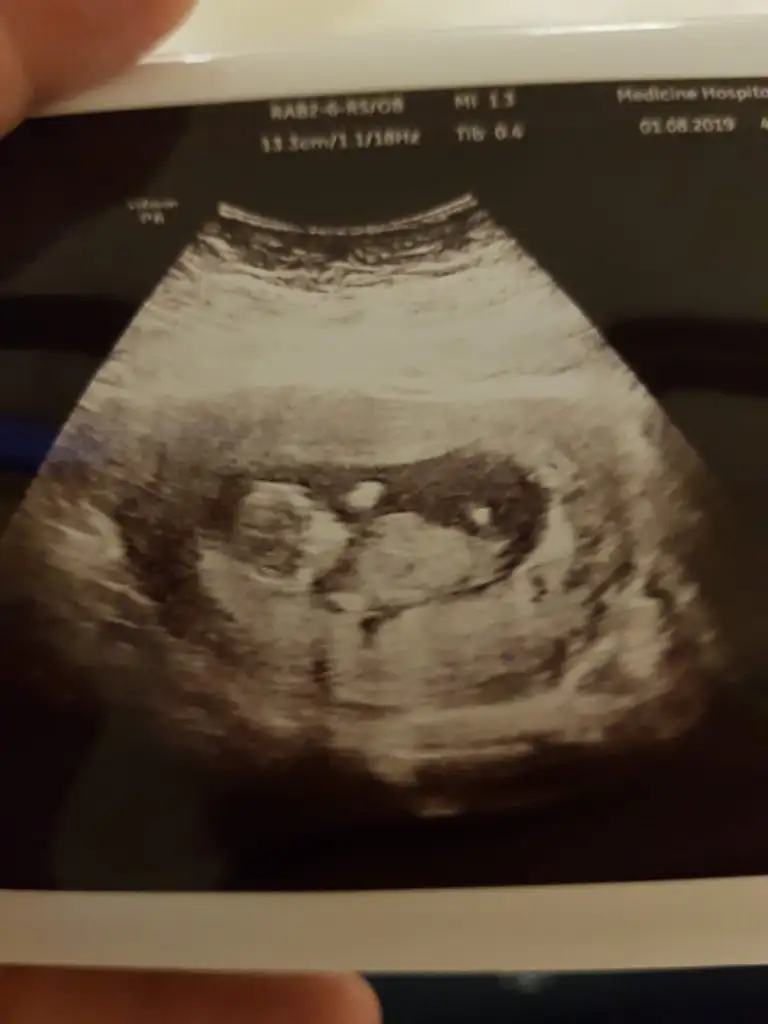

Kizlar tahminu olan varmi 10+2 ciktik bugun

Kizlar bize de tahminde bulursunz sevinirim❣️